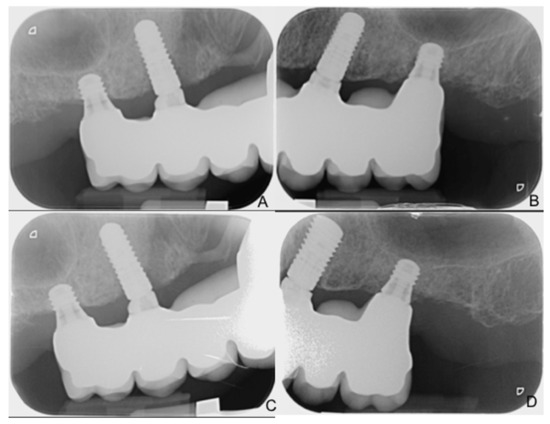

| MBL Short | MBL Control | Progressive Changes Short | Progressive Changes Control | |

|---|---|---|---|---|

| Prosthesis delivering (BL) | 0.17 ± 0.41 | 0.28 ± 0.21 | NA | NA |

| 6 months | 0.18 ± 0.34 | 0.49 ± 0.44 | −0.01 ± 0.11 | −0.21 ± 0.33 |

| 12 months | 0.21 ± 0.35 | 0.58 ± 0.44 | −0.04 ± 0.13 | −0.30 ± 0.32 |

| 18 months | 0.34 ± 0.35 | 0.68 ± 0.51 | −0.17 ± 0.29 | −0.40 ± 0.37 |

| 24 months | 0.44 ± 0.37 | 0.84 ± 0.68 | −0.28 ± 0.37 | −0.54 ± 0.49 |